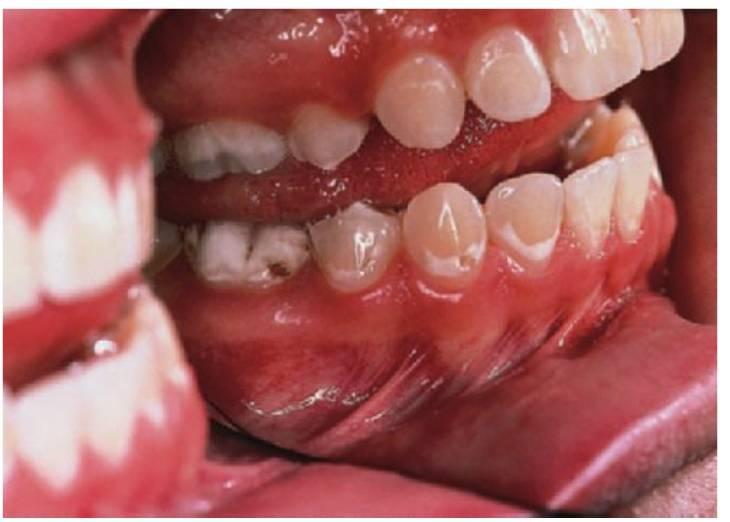

Características de las caries inducidas por el biberón en la infancia temprana

- Las caries rampantes afectan a los dientes anterosuperiores (fig. 3.5).

- Las lesiones aparecen después en los dientes posteriores, los primeros molares maxilares y mandibulares.

- Los caninos están menos afectados que los primeros molares porque erupcionan después.

- Los dientes anteroinferiores no están afectados, se supone que debido al flujo salival y a la posición de la lengua.

- El biberón suele utilizarse como chupete para conseguir que el niño se duerma.

- Las caries de biberón se presentan en todos los grupos socioeconómicos y suelen reflejar la dinámica social de la familia. Los niños que duermen mal o tienen cólicos suelen tranquilizarse con el biberón. El biberón puede contener cualquier líquido con carbohidratos fermentables, incluso leche, si bien suelen usarse con bebidas y zumos que con tienen vitamina C.

- Este patrón de caries puede presentarse también a partir de una lactancia materna a demanda prolongada.